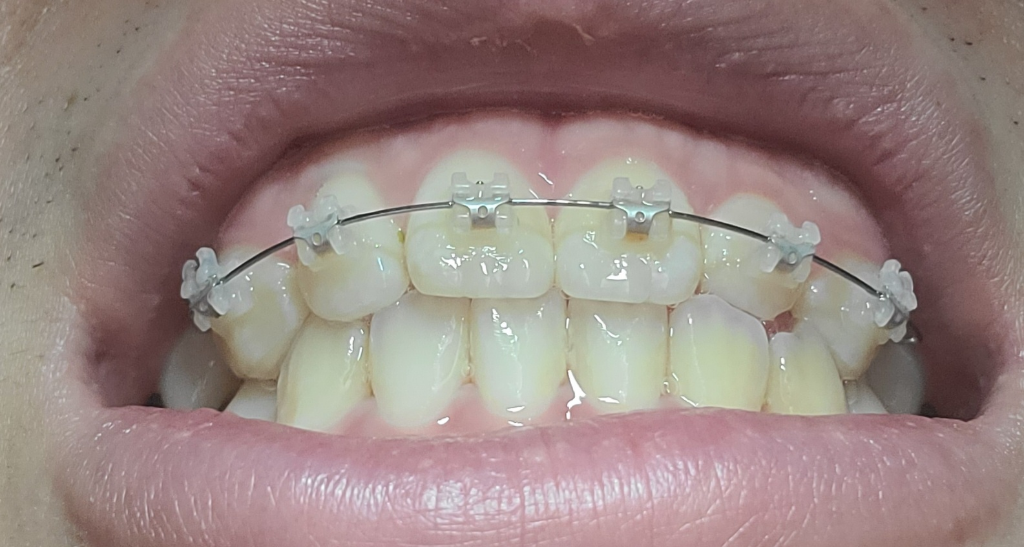

저작을 하지 않았을 때 입을 벌리고 있는 것은 정상적인 생리 반응 중 하나입니다. 따라서 말씀하신 것은 정상이며 치아 교정 후 그런 느낌이 든다는 것은 느낌일 가능성이 크며 교정이 완료될때까지 기다려보시길 바랍니다.

평소 편안하게 계실때에는 치아들은 물리지 않고 약간 떨어져 잇게 됩니다. 치아들이 쉬는시간이죠. 수면시에도 그러면 좋겟지만, 수면시에 이를 꽉깨물거나 이를 가는 습관이 잇다면 치아에 좋지 않겟죠. 교정장치때문에 수면시에 치아가 예민해 져서 그러시는게 아닌가 생각됩니다.